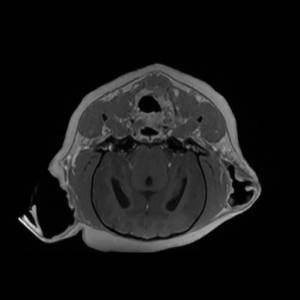

Main Gallery

Playing with a photo gallery function. It is possible to have multiple galleries, each within a namespace.